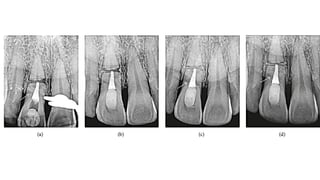

• Various treatment options of Complications:

1) • Root canal therapy for both coronal and apical segment, when they are not separated

2) Root canal therapy of coronal segment and no treatment of apical segment .

3) Root canal therapy for coronal segment and surgical removal of apical third if apical segment is separated

1) Apexification procedure of coronal segment.

2) Intraradicular splint

3) Endodontic implants,

4) Orthodontic extrusion

5) extraction

• Complications • Pulpnecrosis occurs in 25% usually in the coronal segment while the apical segment remain vital. • Calcification is common in vital cases. • Various treatment options of Complications: 1) • Root canal therapy for both coronal and apical segment, when they are not separated 2) Root canal therapy of coronal segment and no treatment of apical segment . 3) Root canal therapy for coronal segment and surgical removal of apical third if apical segment is separated

• 14.

1) Apexification procedureof coronal segment. 2) Intraradicular splint 3) Endodontic implants, 4) Orthodontic extrusion 5) extraction